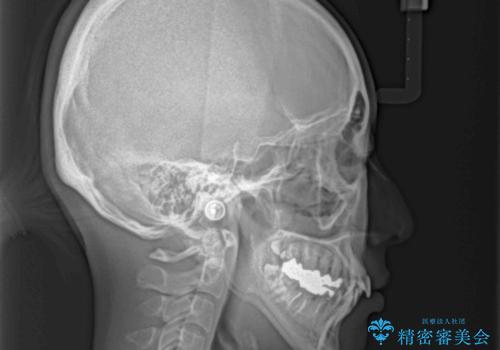

上顎骨拡大を併用したインビザライン矯正

- 上下のデコボコと奥歯の咬みにくさを気にして来院された患者様です。

上顎骨の幅が下顎骨よりも小さいので、拡大装置により骨幅を広げて上下関係を改善し、その後インビザラインにて歯並びを整えることとしました。

上下の骨幅を改善したことで、スムーズに歯列矯正を行うことができました。